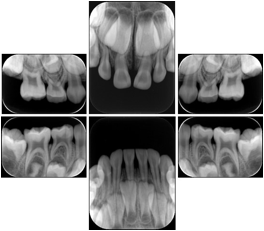

6 Standard Pedodontic A Dental Image Layout

DL-P001A

Reference:

00

Pedodontic

16, 55, 54, 53

01

52, 51, 61, 62

02

63, 64, 65, 26

10

46, 85, 84, 83,

11

82, 81, 71, 72

12

73, 74, 75, 36